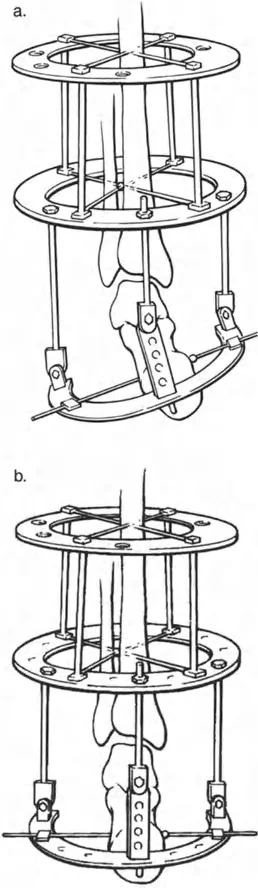

- صورة توضح تقلصًا في الكاحل بزاوية 20 درجة.

- صورة شعاعية توضح تقلصًا في الكاحل بزاوية 20 درجة.

- صورة توضح طريقة الشق الجلدي لتطويل وتر العرقوب.

- صور متتالية توضح خطوات عملية تطويل وتر العرقوب بالشق الجلدي.